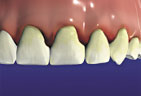

Periodontitis Periodontitis